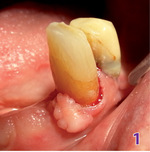

Pacjent został poinformowany o tym, że przed przystąpieniem do wykonania protez zębowych musi poddać się zabiegowi chirurgicznemu, ponieważ na dziąśle w okolicy zęba 33 po stronie mezjalnej widoczna jest zmiana rozrostowa (ryc. 1).

Pacjent nie wyraził zgody na leczenie chirurgiczne i nalegał, aby wykonać protezy bez usuwania zmiany. Lekarz jednak odmówił, tłumacząc, że nie ma możliwości poprawnego wykonania protezy bez prawidłowego odwzorowania podłoża protetycznego, w czym przeszkadzała obecność zmiany dziąsłowej. Dodatkowo pacjent został poinformowany o tym, że jeżeli nawet na bazie takiego podłoża protetycznego zostałaby wykonana praca protetyczna, to na skutek osiadania protez zmiana ta byłaby narażona na przewlekłe drażnienie mechaniczne podczas użytkowania protez, co mogłoby w konsekwencji przyczynić się nawet do transformacji nowotworowej.